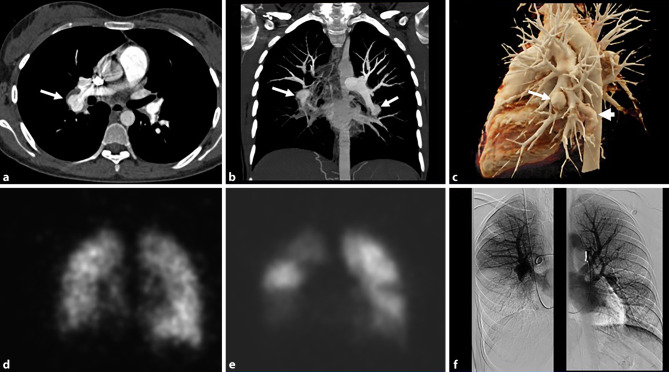

The CT showed a bilateral pulmonary artery aneurysm with wall-adherent thrombi and relatively well-defined walls of the aneurysms (Fig. 1a–c). Furthermore, thrombotic masses in the lumen of subsegmental and segmental arteries were observed. Ventilation-perfusion scintigraphy showed multiple perfusion defects in the lower lobe of both lungs, the apical right upper lobe and the lingula, compatible with CTEPH (Fig. 1d, e). On right heart catheterization, all pressures were normal. Pulmonary angiography showed massive aneurysm of the right lower lobe pulmonary artery with an occlusion of the pulmonary arteries and extensive segmental pulmonary artery aneurysms in the left lower lobe (Fig. 1f).

Fig. 1.

a–c CT pulmonary angiography: a axial reconstruction showing an aneurysm of the right lower lobar artery with wall-adherent thrombus (arrow). b Coronal maximum intensity projection (MIP) shows bilateral aneurysms or pseudoaneurysms of the right lower pulmonary artery and left lower lobe segmental pulmonary arteries (arrows). c 3D-VRT shows pulmonary aneurysm or pseudoaneurysm (arrow) and a varicose aneurysm on the left side (arrowhead). d–e Ventilation (d)-perfusion (e) scintigraphy. Coronal view scintigraphy shows extensive perfusion defects in both lower lung fields, the right upper lung field and left middle lung field. f Digital subtraction pulmonary angiography shows right pulmonary artery aneurysm with lower lobe perfusion defect and left segmental pulmonary artery aneurysm that corresponded to the results of perfusion scintigraphy